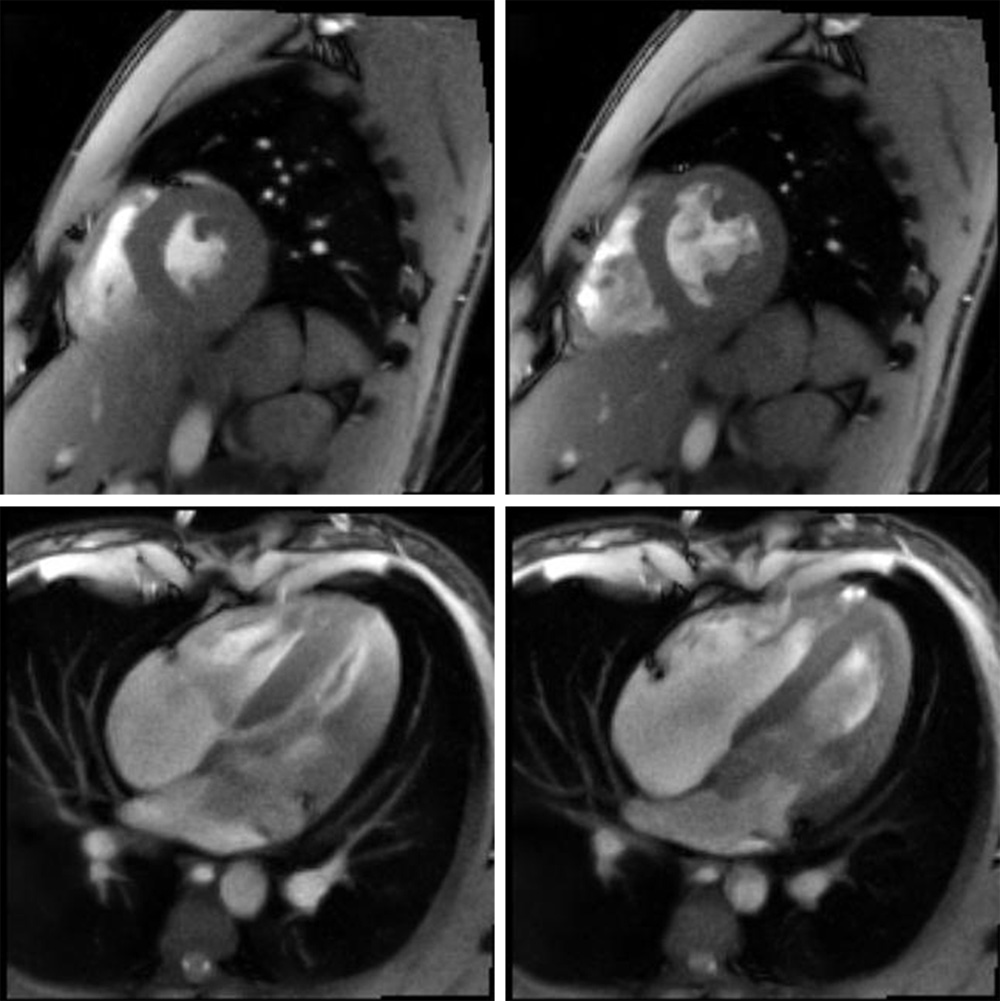

Im Jahr 2010 gelang Frahm und seinem Team ein weiterer Durchbruch, indem sie auch das Problem der hohen Zahl an erforderlichen Einzelmessungen lösten: Mit FLASH 2 stellten sie eine weitere Innovation vor, die ein neues mathematisches Verfahren für die Bildrekonstruktion nutzt und somit nur noch ganz wenigen Einzelmessungen pro Bild auskommt. Das Verfahren beschleunigt die MRT-Aufnahmen noch einmal deutlich. Die Messzeit für ein Bild lässt sich so bis zu einer Hundertstelsekunde reduzieren. Damit ist es nun erstmals möglich, Echtzeit-Filme aus dem Inneren des Körpers aufzunehmen und Gelenkbewegungen, Sprechbewegungen, Schluckvorgänge oder das schlagende Herz „live“ zu beobachten. So lassen sich auch Patienten, die aus gesundheitlichen Gründen den Atem nicht lange anhalten können, im MRT untersuchen. Außerdem könnte die neue Technik in der Zukunft genutzt werden, um minimal-invasive Eingriffe und Behandlungen zu begleiten, die bisher unter Röntgenkontrolle durchgeführt werden.

Klinische Bildgebung als wichtiges diagnostisches Werkzeug ist ohne MRT heute nicht denkbar. Weltweit finden jeden Tag unzählige Aufnahmen statt. Voraussetzung dafür ist die Möglichkeit der schnellen Auswertung. Die Erfindung der FLASH-Technologie durch Jens Frahm und die konsequente Implementierung durch seine Arbeitsgruppe hat somit die Basis für ein diagnostisches Werkzeug geschaffen, ohne das die moderne Medizin nicht denkbar wäre. Die Weiterentwicklung dieser Überlegungen hin zu Echtzeitaufnahmen von bewegten Organen (Bsp. das schlagende Herz) im Rahmen von FLASH 2 stellt einen ähnlichen Innovationsschub wie die FLASH-Technologie dar. Wenn diese Real Time MRT flächendeckend implementiert ist, ergeben sich daraus wiederum ganz neue diagnostische Möglichkeiten. Zusammenfassend hat Jens Frahm durch die konsequente Beschäftigung mit der MRT Fortschritte ermöglichen können, die täglich einer großen Zahl von Patienten zu Gute kommen.

Menschliches Herz: Links eine systolische Kontraktions- und rechts eine diastolische Expansionsphase; oben ein Kurzachsenblick unten ein 4-Kammer-Blick mit 33 ms Auflösung (© MPI für biophysikalische Chemie) -